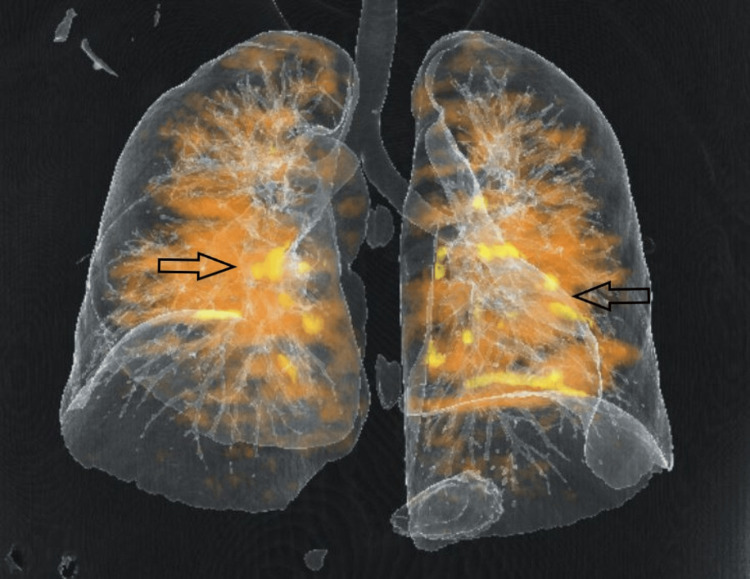

The real-time reverse transcription-polymerase chain reaction (RT-PCR) for COVID-19 was negative. The CT pulmonary angiography revealed multiple filling defects in superior and inferior segmental branches of both pulmonary arteries suggestive of pulmonary thromboembolism (Figures 2–3).